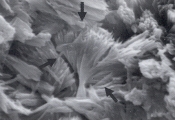

Особенности Цистиновые кристаллы бесцветные, характерной гексагональной формы с равными или неравными сторонами (рис. 25-26). Они могут появляться одиночно, но чаще в виде агрегатов. Их определение требует уменьшения световой интенсивности, так как они тонкие. Цистиновые кристаллы чаще всего формируются в концентрированной кислой моче. Формирование явной щелочной мочи, как следствие инфекции или контаминации уреазообразующими микробами, может способствовать образованию цистиновых кристаллов. Добавление ледяной уксусной кислоты после замораживания и центрифугирования может улучшить определение типичных кристаллов в образцах щелочной мочи. Цистиновые кристаллы нерастворимы в уксусной кислоте, спирте, ацетоне, эфире и кипящей воде. Они растворимы в аммиаке и соляной кислоте. Интерпретация Цистиновая кристаллурия ненормальный феномен. Цистиновые уролиты могут развиваться у собак и кошек с метаболическим расстройством цистинурии. Однако, не у всех пациентов с цистенурией развиваются цистиновые уролиты (см. обсуждение магний аммоний фосфатной и мочевокислой кристаллурии для детальной дифференциации цистиновых кристаллов от струвитов и кристаллов мочевой кислоты). Рис. 25. Микрофотография цистиновых кристаллов в мочевом осадке 2- летнего кобеля английского бульдога с цистиновыми камнями в мочевом пузыре (не окрашено, увеличение Х 250).

Рис. 26. Сканированная электронная микрофотография кристаллов, описанных в рис. 25 (увеличение Х 1,980).